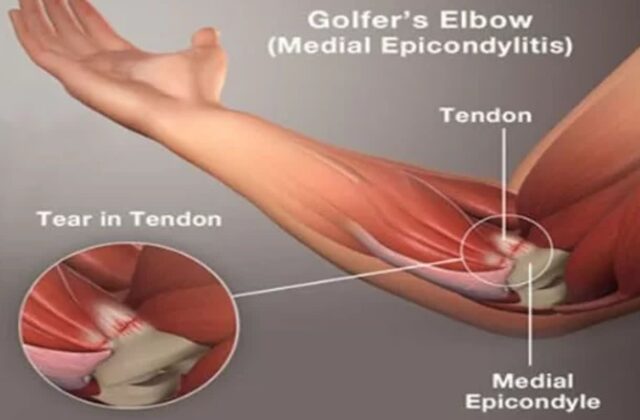

내측상과염 팔꿈치 안쪽 통증 원인 및 증상 골퍼 엘보 의심된다면